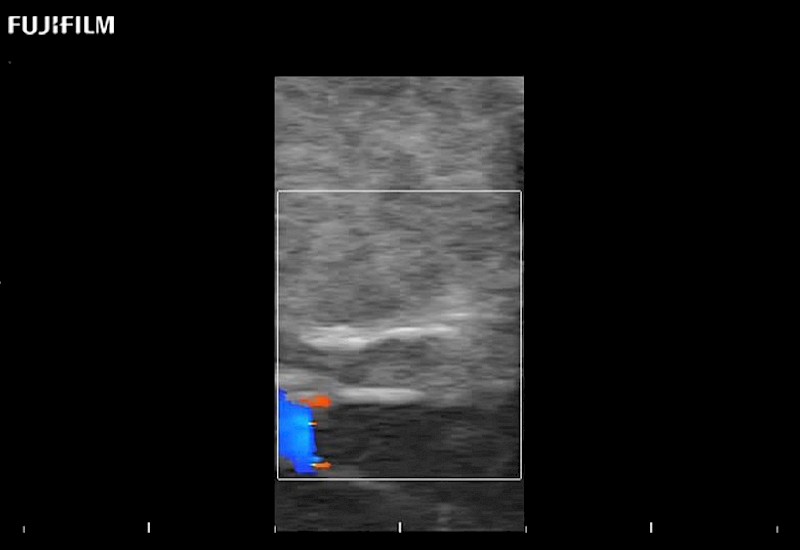

Extraordinary high-resolution digital imaging

Multi-Parametric imaging modalities